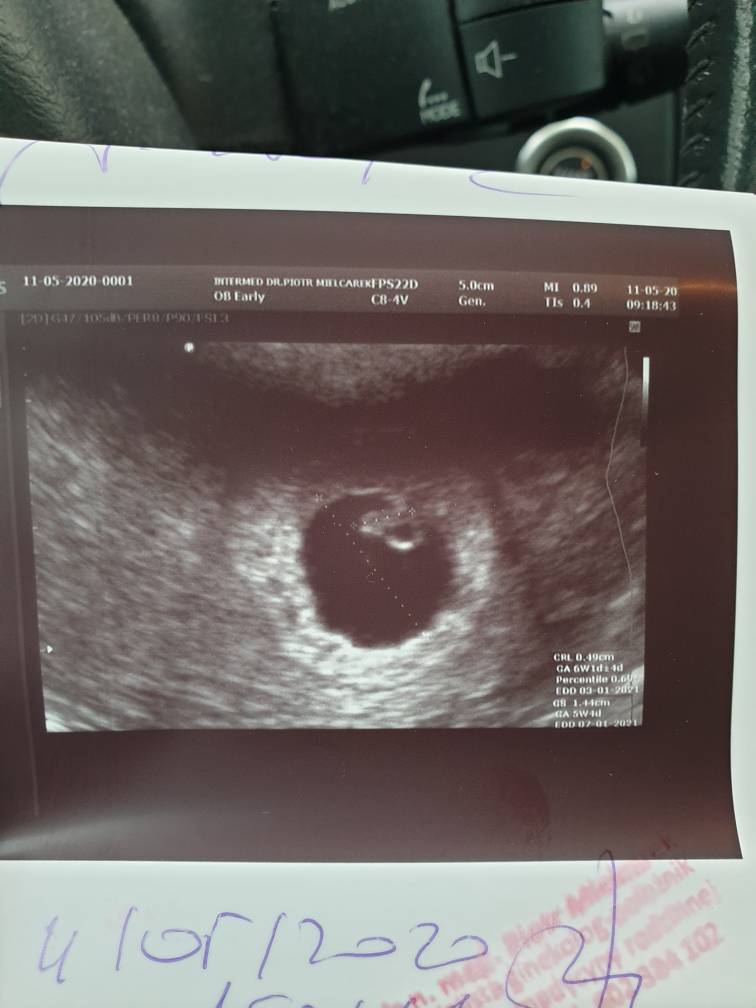

No więc serduszko bije [emoji7] ciąża jest młodsza, wg wielkości zarodka 6+1 zaledwie. Na usg jest zapis +/- 4 dni, cokolwiek to znaczy..Tym samym termin mojego porodu zmienił się na 3-7 stycznia [emoji854][emoji6]